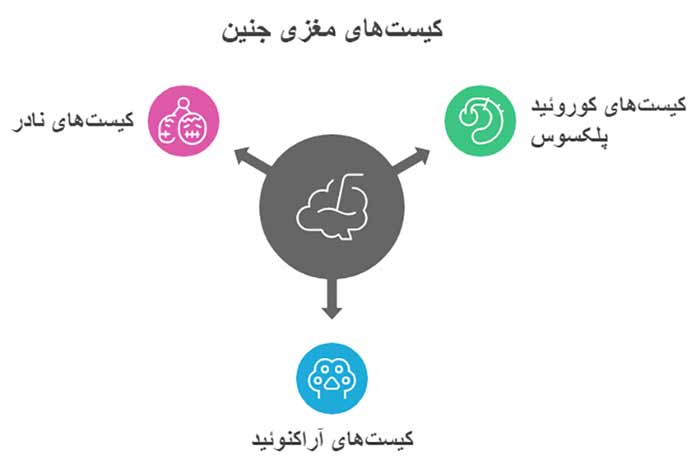

مشکل مغز جنین در سونو آنومالی (3 علت کیست در مغز جنین)

سه علت اصلی کیستهای مغزی جنین

علتهای اصلی کیستهای مغز جنین عبارتاند از:

- رشد طبیعی مغز: کیستهای کوروئید پلکسوس اغلب نتیجه تجمع طبیعی مایع در فرآیند تشکیل کوروئید هستند (90 درصد موارد، UCSF، 2025).

- اختلالات کروموزومی: تریزومی 18 یا 21 ممکن است با کیستها همراه باشد (1 در 3000 تولد، با 30 درصد موارد CPC، Mayo Clinic، 2025).

- عوامل محیطی یا عفونت: عفونتهایی مانند توکسوپلاسموز یا ضربههای خفیف میتوانند کیست آراکنوئید را ایجاد کنند (کمتر از 5 درصد، Fetal Medicine Foundation، 2024).